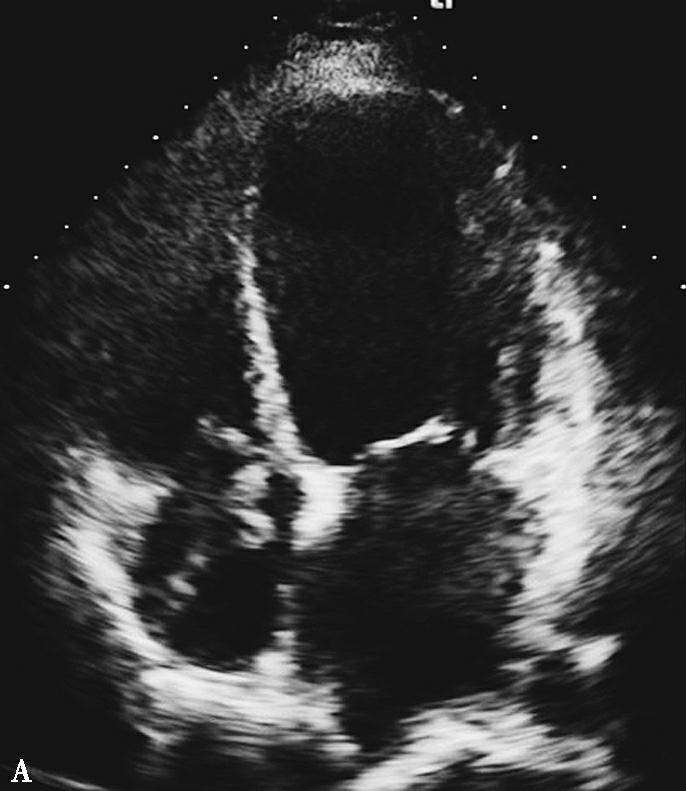

超声心动图:左心室舒张末内径64mm,LVEF 35%,右房内可见不规则条索状、团状等回声,随心脏摆动,舒张期可进入右心室,考虑右房内血栓可能,节段性室壁运动障碍(室间隔、左室心尖部、侧壁心尖段、前壁心尖段、下壁),心尖部室壁瘤形成。

图2抗凝前后超声心动图对比

A图为入院心脏超声心尖四腔切面,可见右房内疑似血栓影,舒张期可进入右心室内;B图为抗凝治疗1周后复查,可见右房内血栓消失